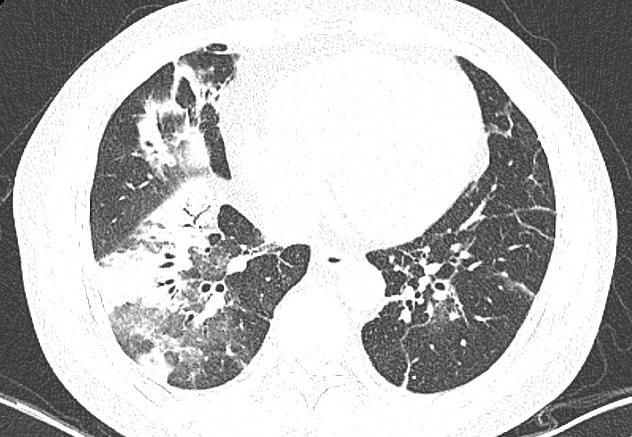

这两位患者症状相似:68岁的黎阿姨(化名)因饲养家鹅后突发高热、干咳,胸部CT显示双肺大面积感染,右肺几乎呈“白肺”;50岁的刘大哥(化名)因从事饲料批发工作常接触鸡群,同样出现不明原因的超高热,影像学也呈现典型的“白肺”表现。两位患者均因高热难退转入广医附属番禺中心医院。

接诊医生通过重点追问禽类接触史这一关键环节,迅速将诊断方向锁定为“鹦鹉热衣原体肺炎”。随后,通过气管镜肺泡灌洗检查和检测结果显示二人为鹦鹉热衣原体感染。

经针对性抗感染治疗,黎阿姨与刘大哥分别在用药后第3天和第2天体温恢复正常,并先后康复出院。这两个病例清晰地证明,对于突发高热伴快速进展肺炎的患者,详尽的环境与职业暴露史问诊是避免误诊、实现精准早期治疗的决定性一步。